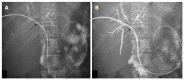

Hilar cholangiocarcinoma is a common malignant tumor of the biliary tree. It has poor prognosis with very low 5-year survival rates. Various imaging modalities are available for detection and staging of the hilar cholangiocarcinoma. Although ultrasonography is the initial investigation of choice, imaging with contrast enhanced computed tomography scan or magnetic resonance imaging is needed prior to management. Surgery is curative wherever possible. Radiological interventions play a role in operable patients in the form of biliary drainage and/or portal vein embolization. In inoperable cases, palliative interventions include biliary drainage, biliary stenting and intra-biliary palliative treatment techniques. Complete knowledge of application of various imaging modalities available and about the possible radiological interventions is important for a radiologist to play a critical role in appropriate management of such patients.We review the various imaging techniques and appearances of hilar cholangiocarcinoma and the possible radiological interventions.